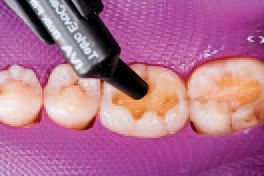

All remaining sharp edges of the preparation were then beveled with Sybron Dental’s Axis fine finishing diamond #846-016, completing the preparations (Fig. 5). Ivoclar Vivadent’s AdheSE® One F self-etch dental adhesive was applied to tooth No. 30 using the VivaPen™ delivery system (Fig. 6), leaving a shiny bonded surface (Fig. 7).